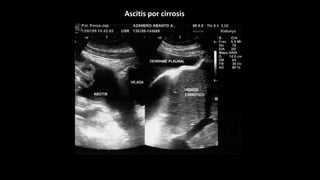

Ascitis es la acumulación patológica de liquido en cavidad peritoneal

75 % se debe a cirrosis hepática con hipertensión portal

La mitad de los cirrótico presentará ascitis en 10 años de evolución.

La Aparición de ascitis determina el empeoramiento del pronostico.

Ante la sospecha clínica de ascitis la ecografía es un método rápido

accesible y altamente sensible que confirma o refuta la existencia de

liquido libre abdominal

Ascitis por cirrosis